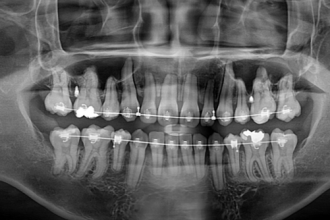

사랑니발치

굿프렌즈 치과 임상 케이스